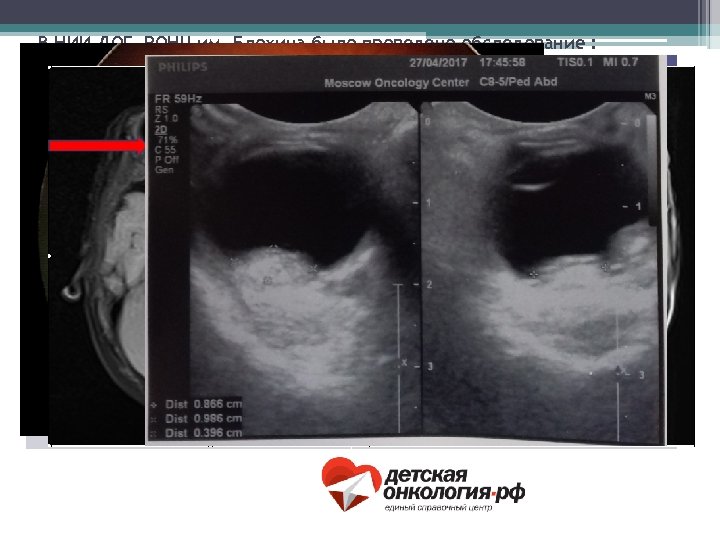

В НИИ ДОГ РОНЦ им. Блохина было проведено обследование : Вид обследования: Заключение: Офтальмологический осмотр, осмотр на ретинальной камере. OD – мультифокальная опухоль OS – анофтальм, без признаков рецидива УЗИ-орбит OD – 2 узловых образования с размерами 0. 5 х0. 2 х0. 4 см и 0. 6 х0. 3 х0. 8 см. OS – анофтальм, без признаков рецидива. МРТ-орбит и головного мозга OD - определяются два объемных образований в нижних отделах 0. 6 х0. 4 х0. 5 см, и в центральнолатеральных отделах(два сливающихся) узла 0. 9 х0. 4 х0. 8 см. OS - анофтальм. В селлярной и супраселлярной областях определяется объемное образвание 2. 3 х1. 7 х1. 8 см.

Состояние после 1 курса СИАХТ: До лечения: После лечения: